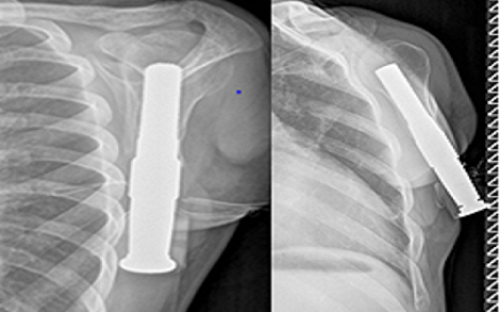

Σε πρώτη φάση ένα στέλεχος από κράμα μετάλλων εμφυτεύθηκε στο οστό το οποίο, αφού ενσωματώθηκε, αποτέλεσε τη βάση για να συνδεθεί ένα εξωτερικό διαδερμικό μέλος. Το τεχνητό χέρι μπορεί πλέον να προστίθεται ή να αφαιρείται με άνεση από το διαδερμικό μέλος. Μετά από μετεγχειρητική νοσηλεία μόλις 7 ημερών, ο νέος εξήλθε από την κλινική απόλυτα ικανοποιημένος δηλώνοντας ότι «το αισθάνομαι σαν το χέρι μου τώρα». Πράγματι, η μέθοδος έχει σχεδιαστεί προκειμένου ο ασθενής, πέρα από τη βελτίωση της κίνησης, να ανακτά την αντίληψη του ίδιου του χεριού του.